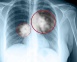

Therapeutic strategies for advanced bladder cancer

Bladder cancer is diagnosed in approximately 540 people in Ireland per year and represents the 14th most common cancer in Ireland.1 Worldwide it is the 13th leading cause of cancer-related death. It is a diagnosis largely seen in older populations with 75% of those diagnosed over the age of 65 years.1 There is a...